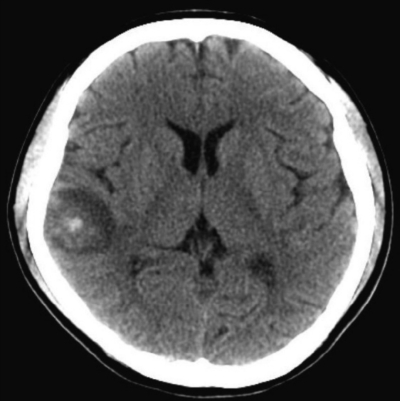

尿所見:蛋白(-)、潜血(-)。血液所見:赤血球 405 万、Hb 11.1 g/dL、Ht 34 %、白血球 2,500(好中球 70 %、好酸球 1 %、好塩基球 1 %、単球 4 %、リンパ球 24 %)、血小板 15 万、PT-INR 1.3(基準 0.9〜1.1)、APTT 38.9 秒(基準対照 32.2)。血液生化学所見:尿素窒素 12 mg/dL、クレアチニン 0.5 mg/dL、Na 140 mEq/L、K 4.0 mEq/L、Cl 108 mEq/L。免疫血清学所見:CRP 0.3 mg/dL、リウマトイド因子<RF>陰性、抗核抗体 1,280 倍(基準 20 以下)、抗 DNA 抗体 60 IU/mL(基準 7以下)、CH50 U/mL(基準 30〜40)、C3 32 mg/dL(基準 52〜112)、C4 3 mg/dL(基準 16〜51)。本日から頭痛、めまい及び嘔吐が出現し、7% 重炭酸ナトリウムを静脈投与されたが改善しない。意識は清明。水平眼振を認める。頭部 CTと頭部 MRI の FLAIR 像とを別に示す。脳脊髄液所見に異常を認めない。